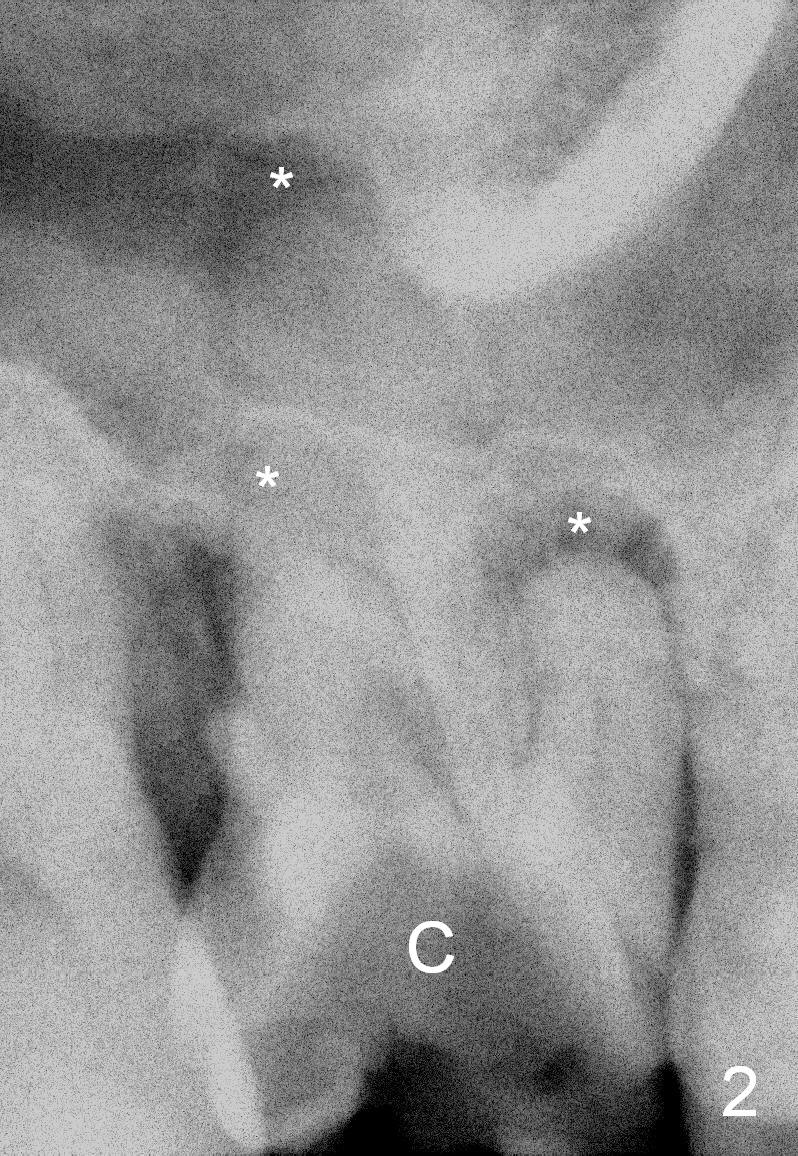

A 43-year-old man will return for #3 implant placement, 2.5 years after extraction. Pre-extraction PAs (Fig.1,2, taken 5 and 2.5 years ago) show that the palatal apex (Fig.1 P) is much higher than the buccal ones (*). The tooth became non-salvageable because of caries (Fig.2 C) in 2.5 years with periapical radiolucency (*). After extraction, the bone available for implantation is probably below the sinus floor (Fig.1,3 arrowheads), 7-9 mm.